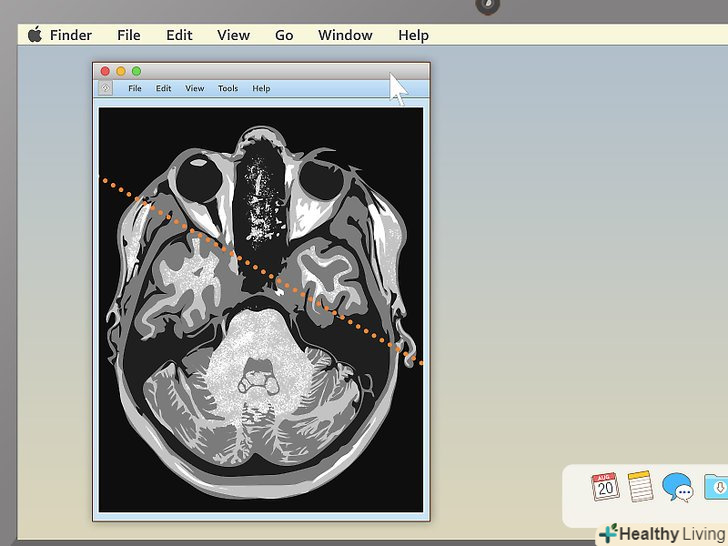

Натисніть на спеціальну лінію, щоб побачити, де перетинаються проекції.якщо ви вирішите відкрити зображення з пересічними проекціями, ви побачите особливу пряму лінію, що перетинає зображення. Вона буває не на всіх записах. Якщо на вашій її немає, на другому знімку буде показано, де знаходиться область перетину. [7] ви зможете зміщувати лінію до центру, направо і наліво. Це дозволить розглянути органи під іншим кутом.- Лінія також вкаже, з якого боку був зроблений знімок. Наприклад, якби МРТ був знімком звичайного предмета (наприклад, дерева), лінія вказала б вам на те, звідки була спрямована камера: зверху з літака, з вікна другого поверху або з землі.

Перетягніть лінію, щоб розглянути різні області на знімку.це дозволить вам переміщатися всередині зображення. Знімок буде автоматично змінювати проекцію.- Наприклад, якщо ви розглядаєте зображення хребта в саггитальной площині і також завантажили область з пересічними площинами, рухаючи лінію, ви зможете вивчити хребці як зверху, так і знизу. Цей інструмент особливо корисний для діагностування грижі міжхребцевих дисків.